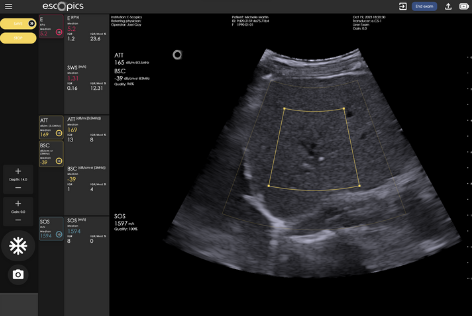

Quantitative Ultrasound

Measurements of liver brightness

3 parameters related to liver steatosis

Reproducible and repeatable quantitative measurements performed in real time, under image guidance

The Q.US Technology

Quantifying steatosis in the liver is the first step in the diagnosis of MASLD and primarily uses non-invasive ultrasound. Initially visual (qualitative), the assessment of fat in the liver has benefited from the development of quantitative ultrasound (QUS) which now offers objective measurements of steatosis-related parameters, surpassing subjective visual assessments.